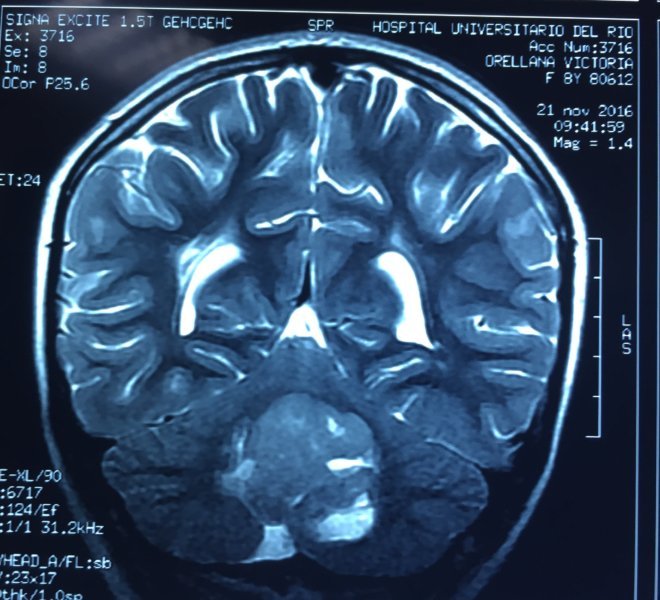

MEDULOBLASTOMA

DESCRIPCIÓN